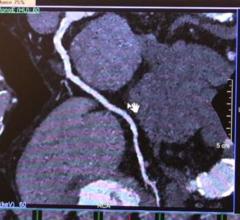

This channel contains news about the Society of Cardiovascular Computed Tomography (SCCT), including coverage of its annual meeting and links to recently released practice guidelines. SCCT is a leading resource for the subspecialty of cardiac computed tomography angiography (CTA or CCTA).

DAIC Editor Dave Fornell explains some of the most innovative new cardiovascular CT technology displayed at the Society ...